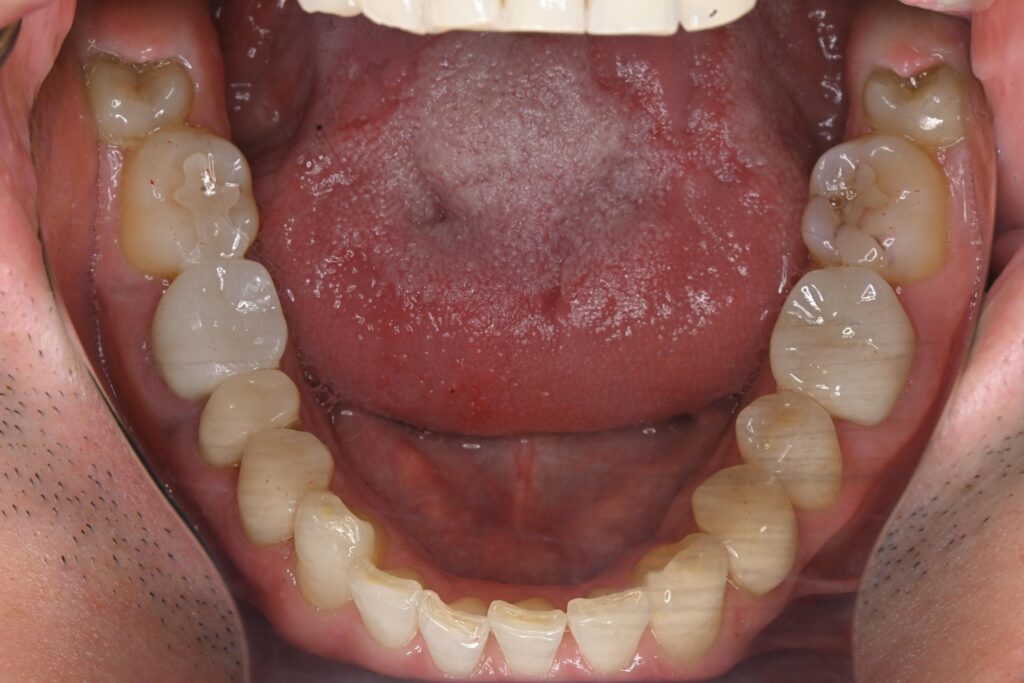

初診時の口腔内の状態:

口腔内には多数の銀歯(銀合金)が確認されました。患者様は過去に多くの虫歯治療を受けており、そのほとんどが保険適用内の銀合金で修復されていました。

患者様はパッチテストによりニッケルなどに対するアレルギーを持っていることが確認されており、口腔内の銀合金もアレルギーの原因となっている可能性が高いと診断しました。また、レントゲン画像を確認すると、被せ物や詰め物の内部、あるいは隙間から、虫歯(カリエス)や根の細菌感染が疑われる状態も確認されました。

古い金属を撤去し、開けてみて確認された虫歯(カリエス)を除去し、型取りを行い、その後被せ物を装着するというシンプルな工程で進めました。

一部の歯(右下の5番目)については、銀歯の詰め物の隙間から細菌が侵入し、歯の根の中が細菌感染している兆候が見られたため、この機会に歯の内部の消毒(根管治療)を挟んで処置を行いました。